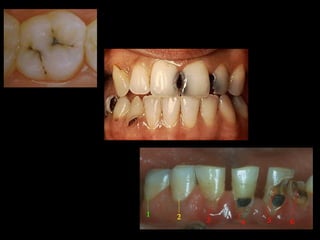

Caries dental:

enfermedad,

infecciosa,

bacteriana,

transmisible,

multifactorial

que provoca la destrucción de

órganos dentarios presentes en boca a

cualquier edad.

Caries dental: enfermedad, infecciosa, bacteriana, transmisible, multifactorial que provocala destrucción de órganos dentarios presentes en boca a cualquier edad. NOM-013-SSA